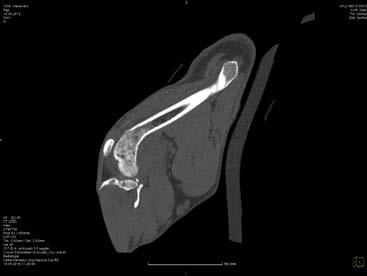

Computer Tomografia

Computer Tomografia (CT) sau Tomografia Axială Computerizată este o tehnică de diagnostic imagistic care furnizează imagini tomografice (adică secțiuni sau straturi corporale), vizualizând organele și țesuturile în funcție de densitatea lor, măsurată grație atenuării unui fascicul de raze X care traversează pacientul din direcții diferite; imaginile stratului respectiv vin reconstruite cu ajutorul calculelor complexe realizate

Vol VI - Nr. 11 (2/2019) 76

de computer. Vizualizarea tomografică elimină problema suprapunerii, prezentă în cadrul examenului radiologic.

Formarea imaginii CT

Un strat al corpului, mai gros sau mai subțire, este traversat de un fascicol de raze X puternic colimat, produs de un tub care se rotește în jurul pacientului într-o manieră consensuală, cu detectorii așezați de o parte și de alta a pacientului.

Datele referitoare la atenuarea fascicolului, obținute din diverse unghiuri, sunt trimise la un calculator care, prin intermediul unor algoritmi matematici complecși, reconstruiește imaginile structurilor anatomice prezente în stratul considerat. Pentru reconstrucția imaginii obiectului se utilizează metoda retroproiecției: pentru fiecare proiecție, imaginea relativă proiectată este “retroproiectată”. Pentru a elimina sau atenua estomparea care tinde să se producă de-a lungul marginilor imaginilor obiectelor retroproiectate, intensitatea măsurată de detectori este filtrată, existând diverse filtre care accentuează mai mult sau mai puțin “curățirea” marginilor (filtre de os, de țesut moale etc.).

Densitatea țesuturilor este exprimată printr-o scară de gri, având la bază unități (sau numere) Hounsfield (HU), numite astfel în memoria inventatorului CT-ului. Unitatea Hounsfield sau numărul CT reprezintă o valoare dimensională proporțională cu densitatea țesutului. Unitățile Hounsfield fac referire la densitatea apei care, prin convenție, este egală cu 0. Peste și sub această valoare sunt localizate densitățile diferitelor țesuturi, extremele fiind reprezentate de -1.000 pentru aer și +1.000 pentru compacta osoasă. Cele mai multe țesuturi moi și a lichide organice au o densitate cuprinsă între +100 și -100 HU. Prin urmare, atunci când se descriu organele și țesuturile, acestea pot fi hiperdense, hipodense sau izodense, în comparație cu alte organe sau țesuturi ori luând ca și referință densitatea apei. Scara de gri este similară celei din radiologie: atenuare majoră= alb, atenuare minoră= negru. După reconstrucția imaginii CT, sunt posibile o serie de operațiuni care poartă denumirea de post-procesare, fiind posibilă îmbunătățirea sau suprimarea informațiilor prezente în imaginile date. Se reușește, astfel, distingerea chiar și a diferențelor mici de densitate (până la 0,5%) și reprezentarea cu nivele de gri diferite. Acest lucru se traduce printr-o rezoluție de contrast mai mare, comparativ cu examenul radiografic.

Examenul CT furnizează imagini tomografice axiale, tăiate perpendicular pe axul sagital median care, așa cum am zis, elimină problema suprapunerii diferitelor structuri anatomice (fig.